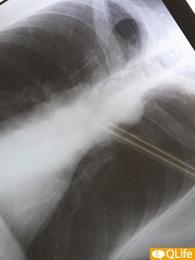

88歳の父が転倒し、大腿骨頚部骨折で入院しました。2ヵ月半で退院できることになり、退院前にドクターが「咳が気になる」と言って、胸部X線写真を撮ってくれました。その結果、肺がんの末期状態であることがわかったのです。